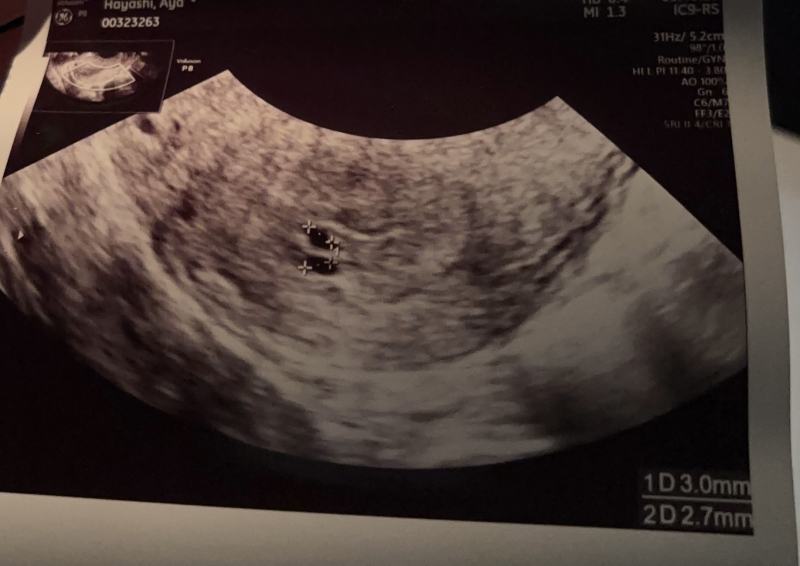

2月24日に病院に行ったのですが胎嚢のみで3mmと

2.7mmでした。

計算的に行くと6週後半ですがそれにしては小さすぎて

赤ちゃんが見えませんでした。

胎嚢の中に白い点のようなもの(卵黄囊)があるように見えるのですが気のせいですか?

胎嚢が二つだったということであると、双子ちゃんの可能性もある様でしたら、より成長はゆっくりなこともある様です。